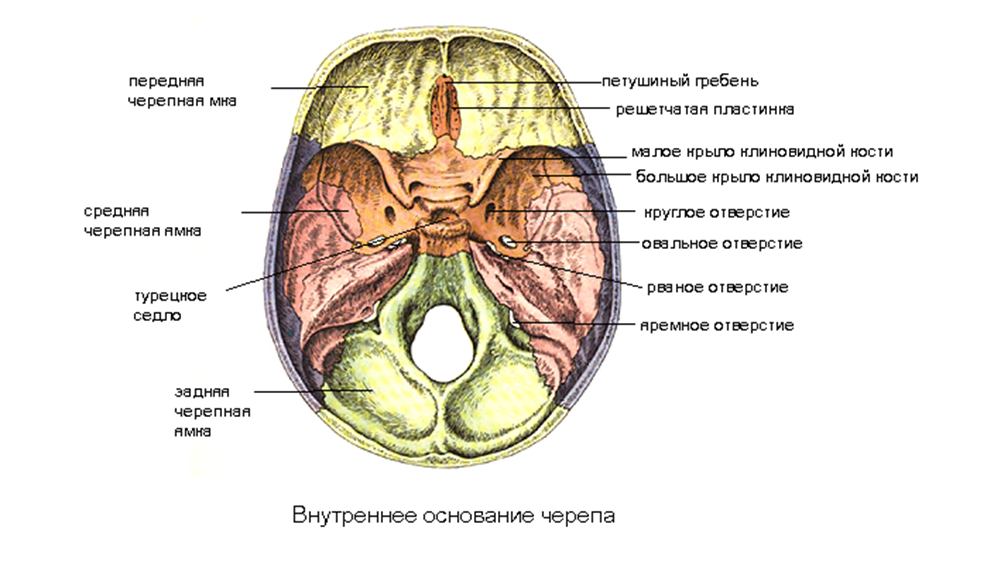

Анатомические детали: Фотографии топографии черепа с нижнего вида